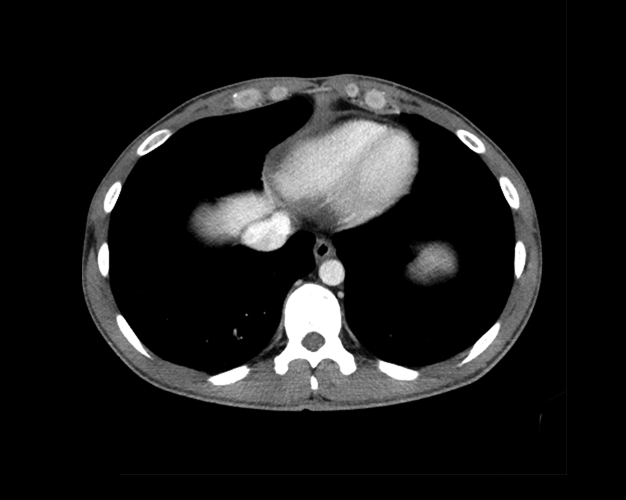

Chest

Covers basic chest radiograph and chest CT anatomy.

Cardiac

Covers basic cardiac CT anatomy.